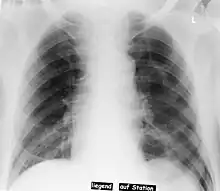

| Pneumothorax left sided | |

In radiology, the deep sulcus sign on a supine chest radiograph is an indirect indicator of a pneumothorax.[1][2] In a supine film, it appears as a deep, lucent, ipsilateral costophrenic angle[3] within the nondependent portions of the pleural space as opposed to the apex (of the lung) when the patient is upright. The costophrenic angle is abnormally deepened when the pleural air collects laterally, producing the deep sulcus sign.[4]